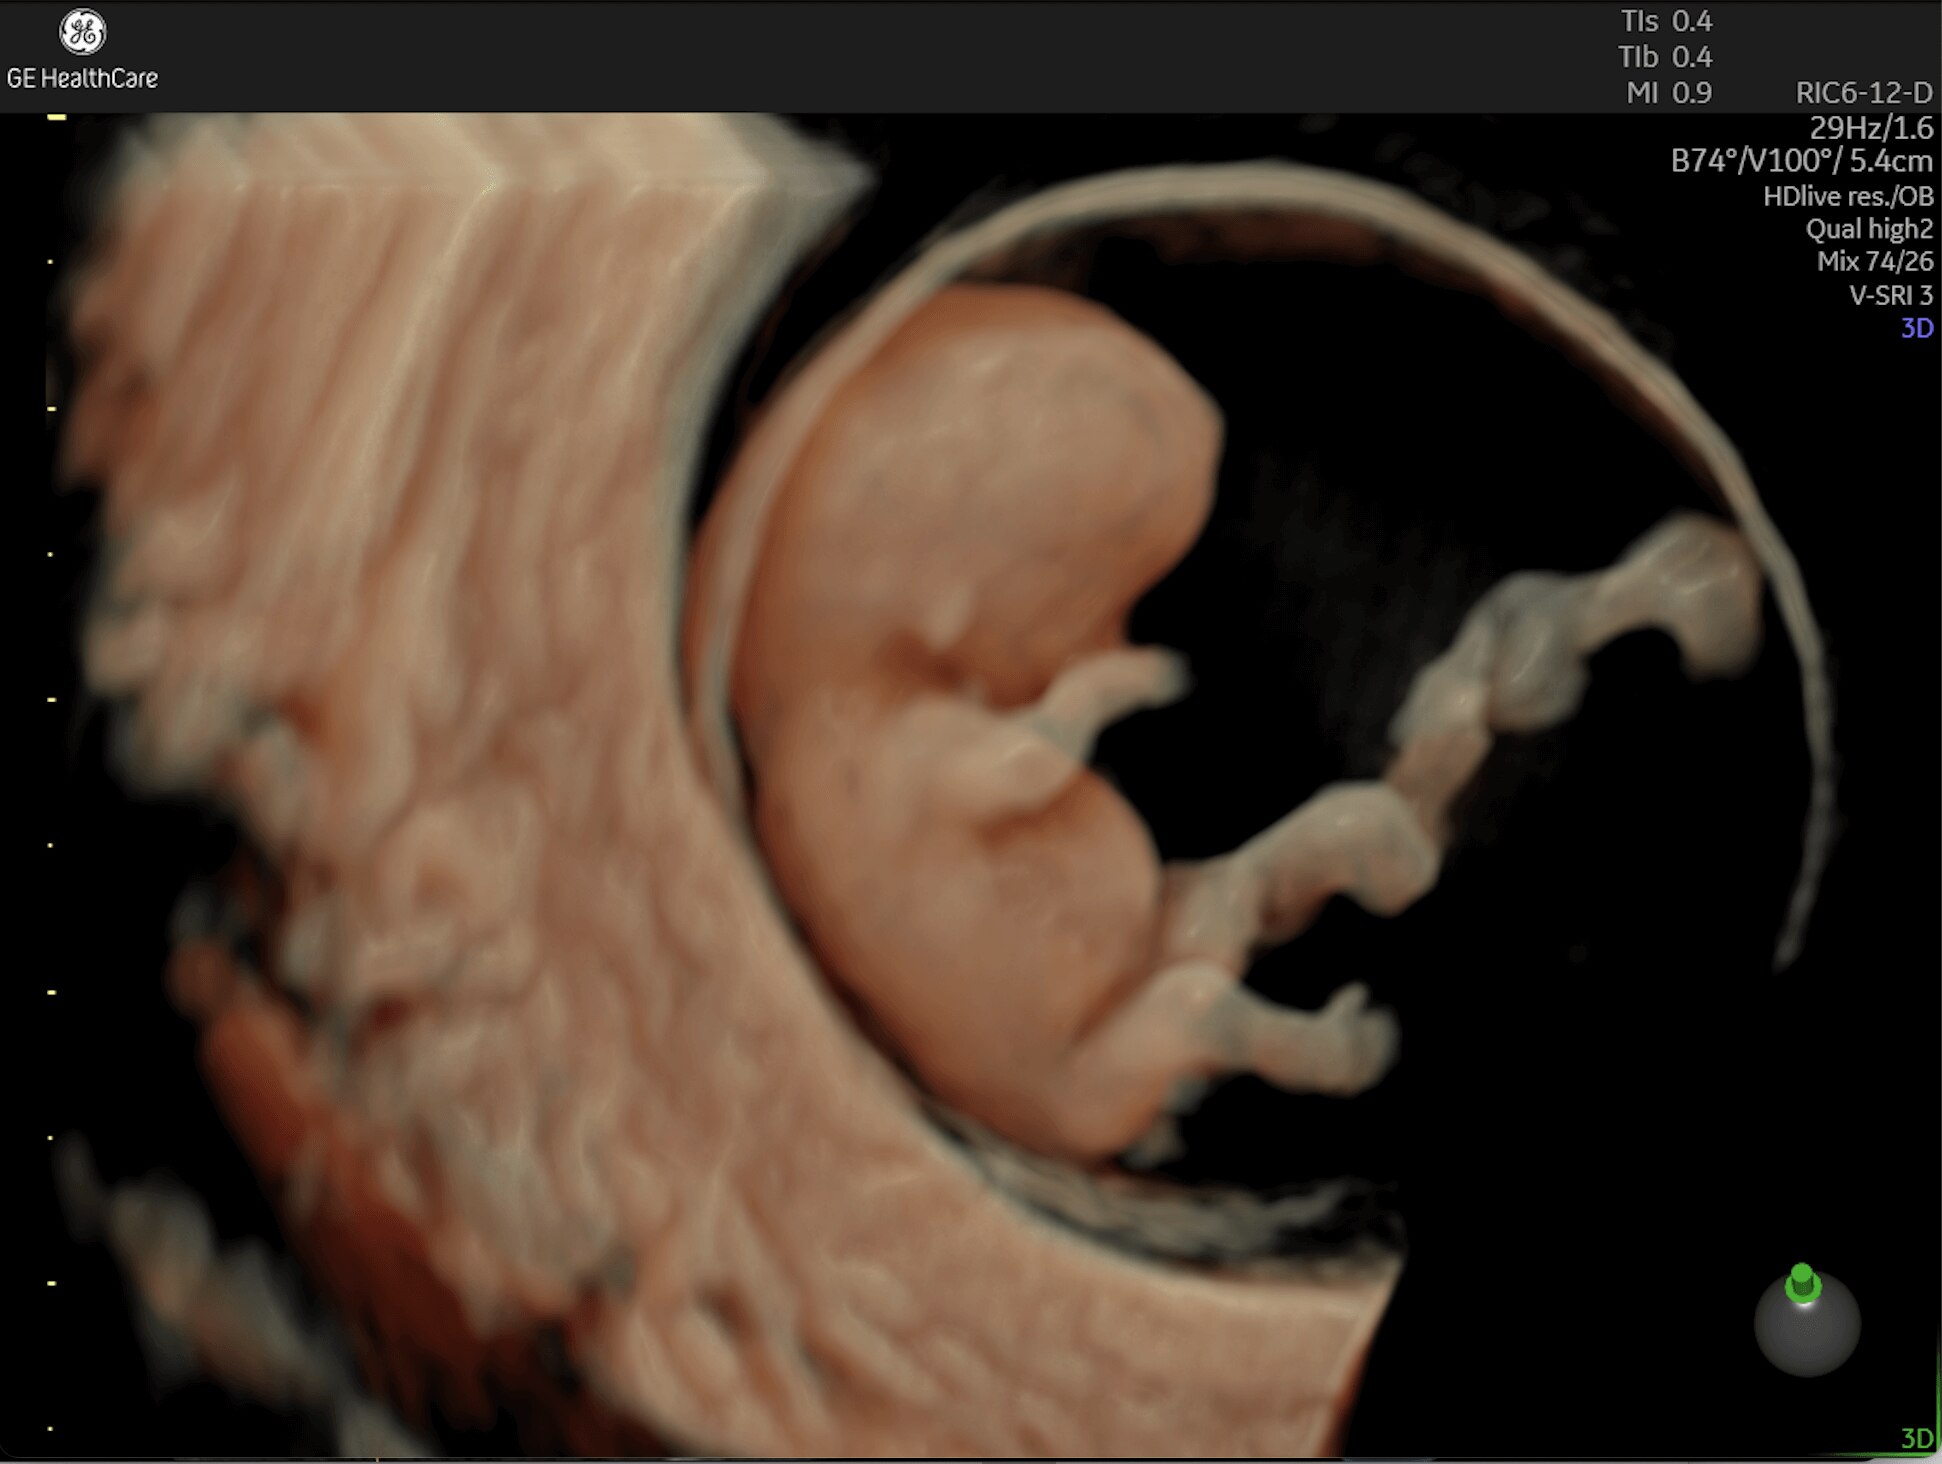

First Trimester Exams

Perform detailed exams with high-resolution for early insights to fetal health

Complex cases come with enough uncertainty. That's why the Voluson Expert 22 is specifically designed for in-depth assessment of complicated anatomy — with pioneering first trimester, fetal cardiac, gynecological, and other pivotal technologies that focus on early detection and intervention.

Identifying fetal cardiac abnormalities earlier means you can intervene sooner, plan for delivery, and potentially improve outcomes. The Voluson Expert 22 provides a full solution of progressive tools, to help distinguish the tiniest structures with stunning clarity to provide patient answers faster.